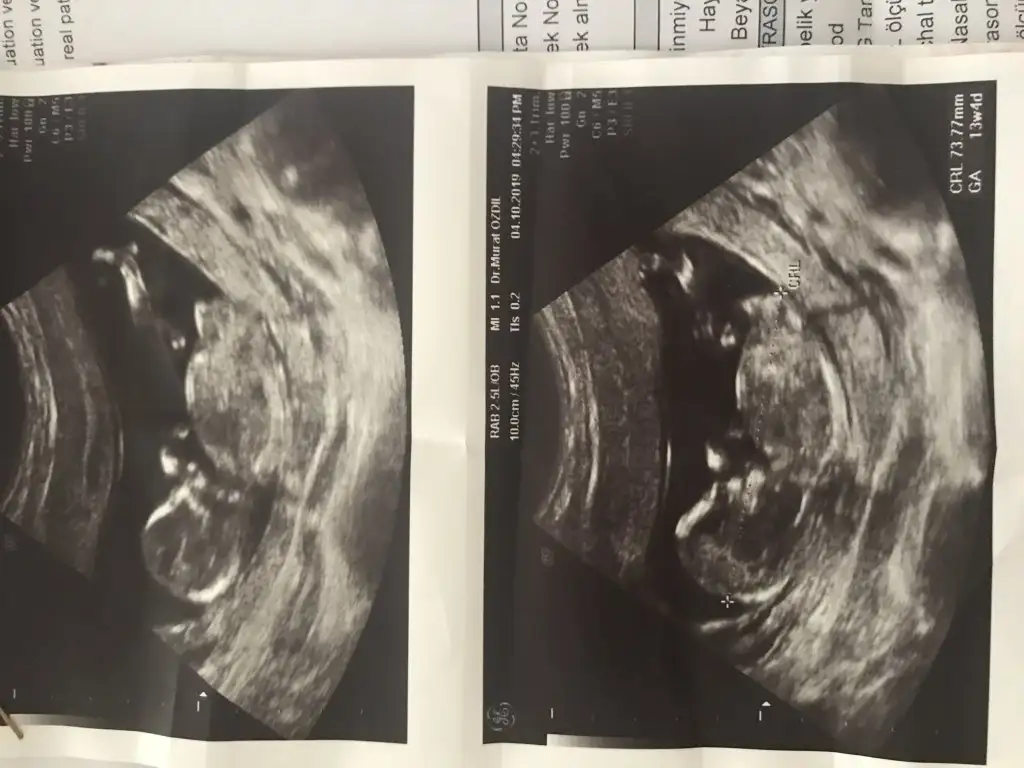

saglıkla gelsin prensesIkra Meyra merhaba cinsiyeti öğrendik kızımız olacakmışBu da son ultrason fotoğrafımız 13 haftalık

Biliyorum erken ama sabirsizim şuan 8+4Tahminim neydisaglıkla gelsin prenses